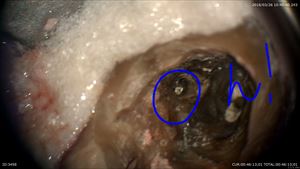

今日から根管治療。。リーマー。。。。次から次へと試練が!!

これもマイクロスコープを使用し除去

感染も

綺麗に

これで大丈夫!!